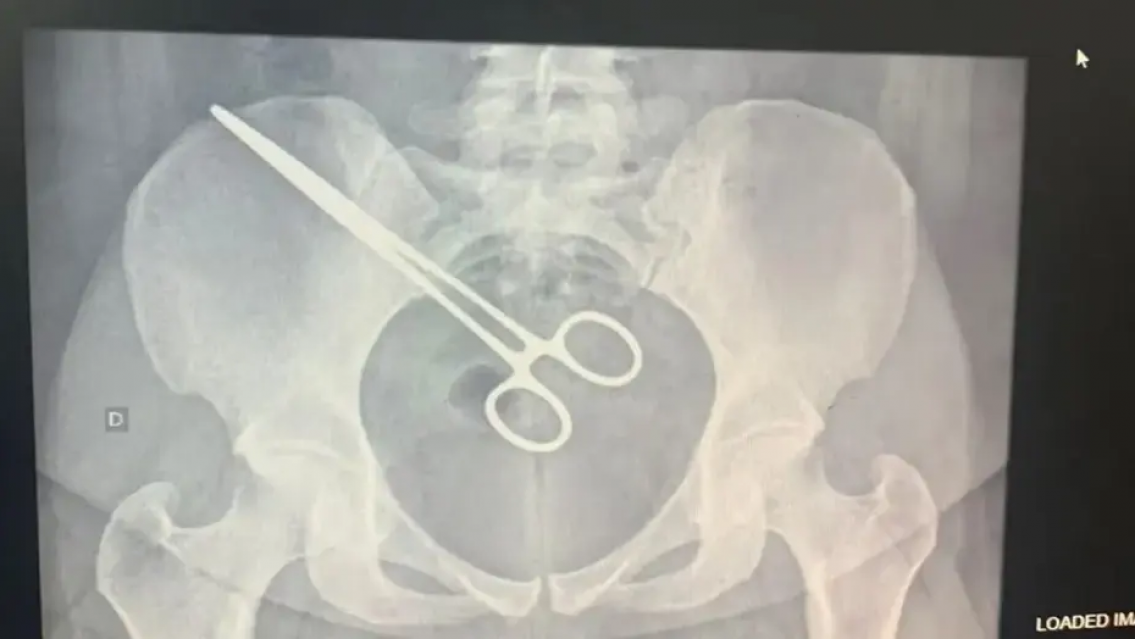

En Brasil, una mujer 27 años descubrió que había unos fórceps quirúrgicos dentro de su cuerpo cuando pasaba por un detector de metales de la prisión en la que se encuentra detenido su marido.

Cuando se presentó en el Centro de Detención Provisional de São José do Rio Preto, San Pablo, se percató que había unas tijeras en la región pélvica de su organismo.

La suegra de la joven dijo que, en septiembre, fue operada en Santa Casa de Araçatuba para extraer un feto que se estaba generando en las trompas uterinas.

Luego del episodio, la paciente acudió al hospital Santa Casa, donde le hicieron un examen de rayos X y encontraron que la pinza estaba dentro de ella.